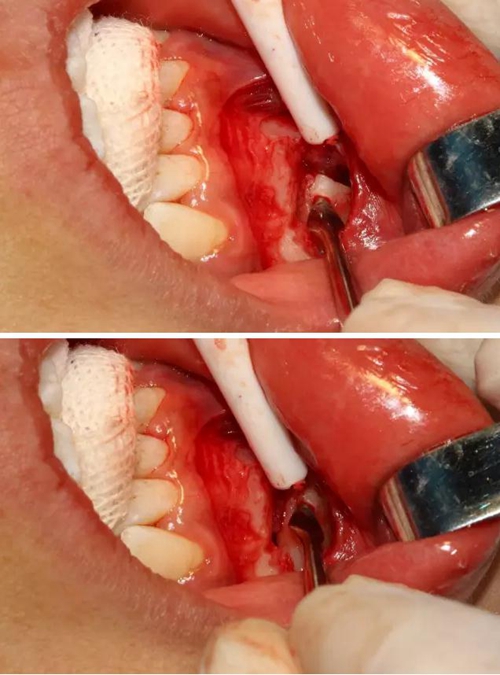

為了減少骨創(chuàng),“T”型分割牙冠

去除冠部

同時在剩余的根部斷面4MM下,預(yù)備2MM的溝槽,通過剝離子的三角尖端將牙體推出